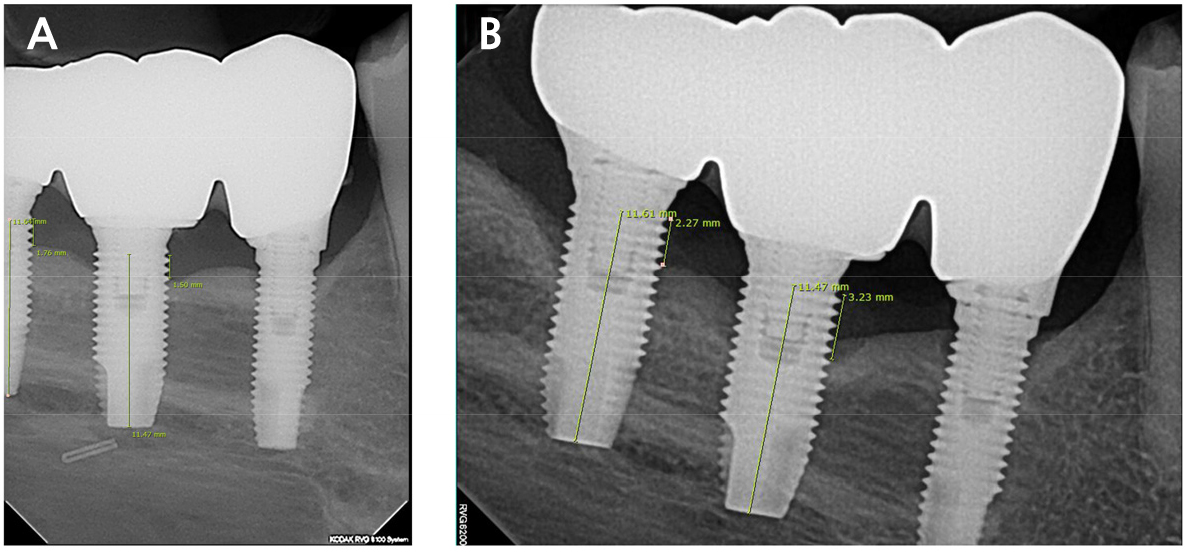

Fig. 1.

Measurement of MBL and implant length. The actual fixture length of #46i and #47i were both 11.5 mm. (A) Periapical radiograph 1 year after implant placement, (M.R #46i: 0.997, #47i: 1.012) (B) Periapical radiograph 3 years after implant placement. (M.R #46i: 0.997, #47i: 1.009), As for MBL, #46i increased from 1.5 mm to 3.2 mm, and #47i increased from 1.7 mm to 2.2 mm.

The criteria for failing implants was set at a vertical bone loss below 1 mm during the first year and 0.2 mm for each subsequent year, as proposed by Albrektsson et al.8 Marginal bone loss (MBL) was measured by comparing the panoramic or periapical radiographs taken at different time points. The number and period of failing implants were evaluated based on the time and length at which abnormal MBLs were detected. MBL was measured using the length measurement tool in INFINITT PACS M6 (Infinitt Healthcare, Seoul, Korea). After measuring the fixture length on radiographs, the magnification ratio (MR) was calculated by dividing the value by the actual fixture length. The distance from the crestal bone, with marginal bone loss, to the upper part of the fixture was measured. Finally, this value was divided according to the MR. The measured MBL values were rounded to two decimal places. (Fig. 1).